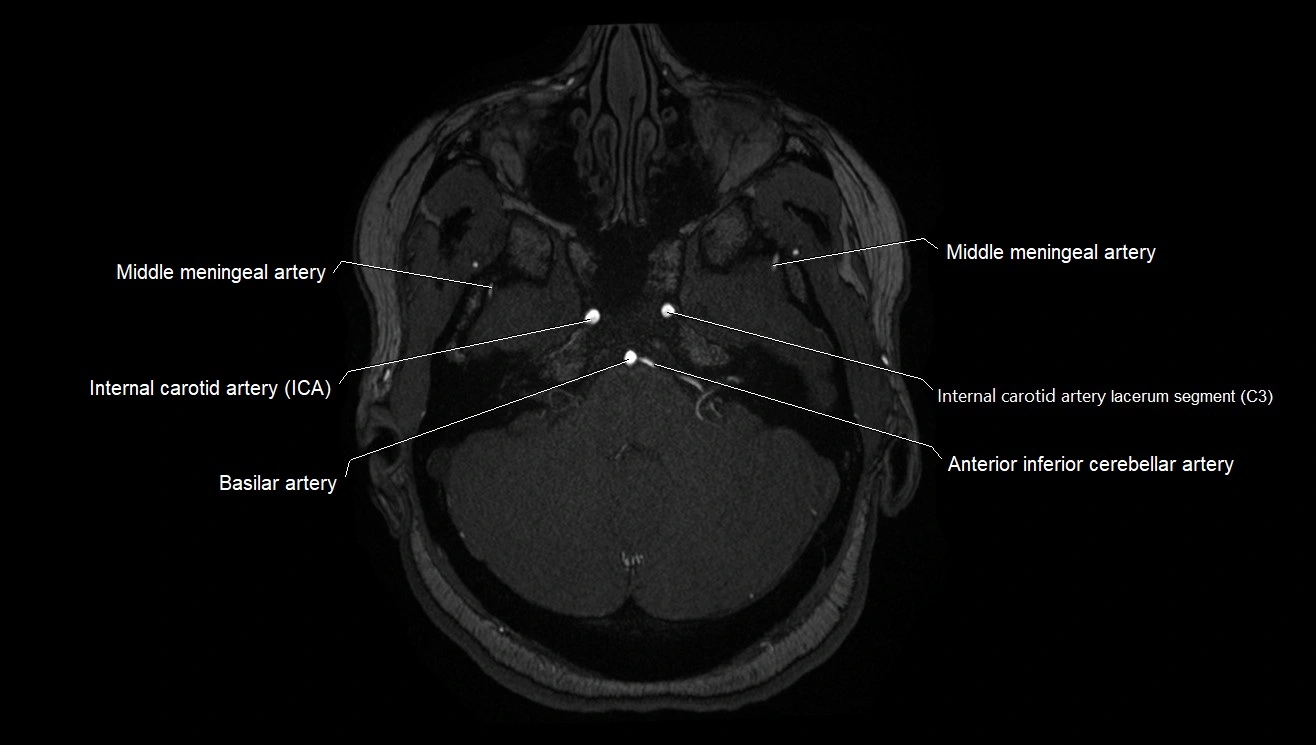

MRA (Magnetic Resonance Angiography):

• Flow-related enhancement makes the AChA appear as a bright, linear vascular signal against suppressed background

• High sensitivity for origin and proximal course; distal branches may be too small to resolve

• Detects stenosis, occlusion, aneurysm, AVM feeders

MRI images

image